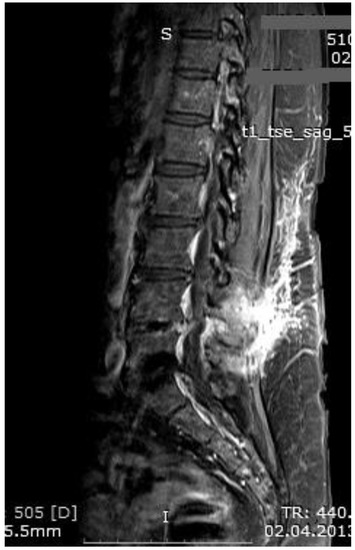

Figure 3. MR imaging T1-weighted scan showing inflammatory infiltrates in the course of pre-HBO2 treatment.

Medicina 55 00164 g003

Figure 4. MR imaging T2-weighted scan showing inflammatory infiltrates in the course of pre-HBO2 treatment.

Medicina 55 00164 g004

Figure 5. MR imaging scan showing inflammatory infiltrates at the end of HBO2 treatment.

The mean number of total HBO2 sessions was 33 (±18.5) sessions. The HBO2 treatment was tolerated well by all patients except two. One patient had to receive analgesics (non-steroidal anti-inflammatories) before HBO2 sessions because she had severe back pain, and in one patient the treatment was interrupted for five days because of minor middle ear barotrauma. Improvements in clinical evaluations and laboratory findings were observed in all cases at the end of the HBO2 therapy. The mean erythrocyte sedimentation rate (ESR) value reduced from 76.1 (range, 6–129) to 45.7 (range, 5–81) mm/h, and the mean C-reactive protein (CRP) concentration reduced from 82.9 (range, 14–202) to 17.5 (range, 1–49.5) mg/L (normal limits; ESR: <20 mm/h, CRP: 0–5 mg/L). Infection resolution was adequately achieved in 12 of 13 patients on MR imaging at the end of HBO2 treatment or during the first month of follow-up (Figure 3, Figure 4 and Figure 5). There was no significant improvement in one patient. To extend the total clinical follow-up period up to three years (mean: 11 months; range, 1 month–3 years), telephone interviews were conducted to determine any recurrence of symptomatic clinical infection. No recurrence of infection, spinal instability, or deformity was seen in any patients.